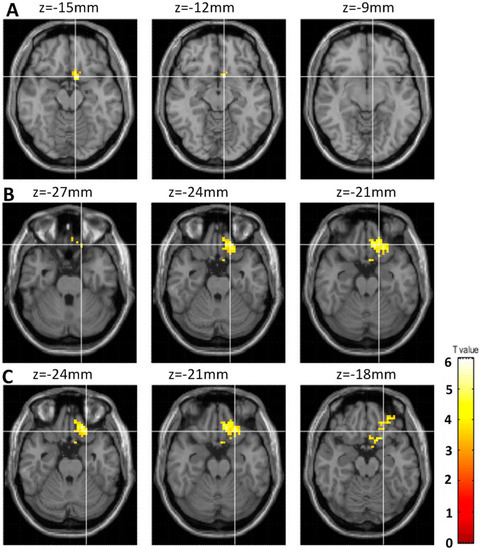

3.2. Comparison of the Changes in fALFF between Student Pro-Gamers and IGD Adolescents after a Year

4.2. Increased Brain Activity within the Attention Network (parietal lobe) in Response to One-Year Internet Gameplay in Both Groups

4.3. Increased Brain Activity within the Orbitofrontal Cortex of the IGD Adolescents in Response to a Year of Internet Gaming

4.4. Association between fALFF Values within the Orbitofrontal and the CBCL-Externalizing Scores